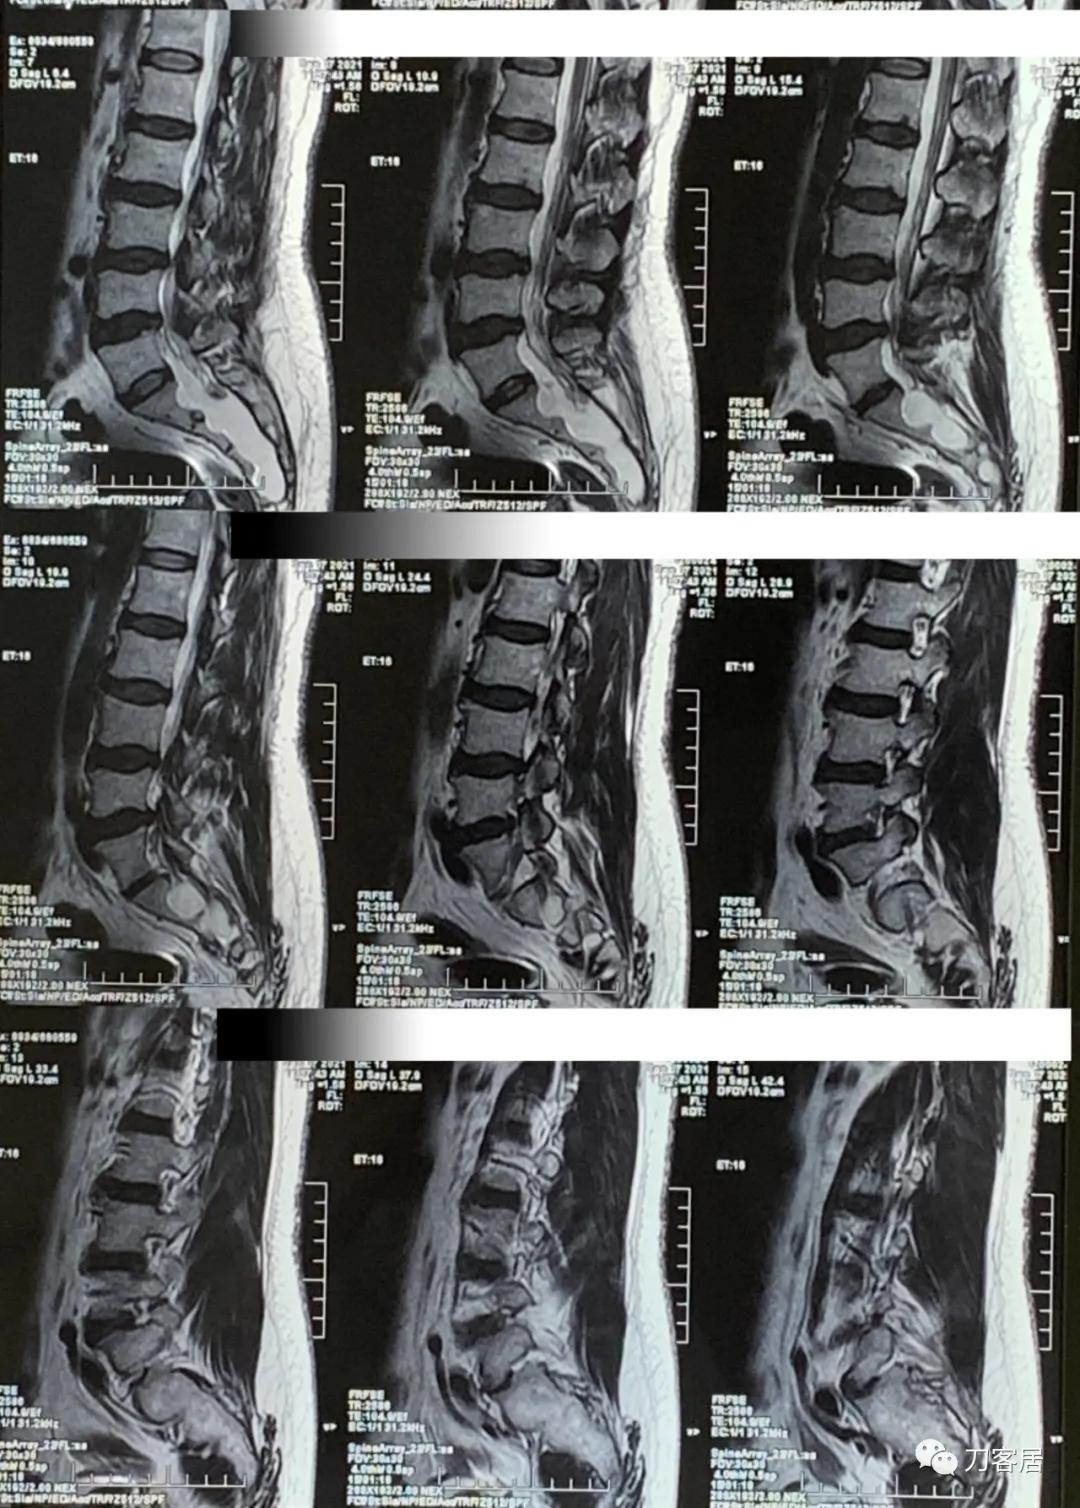

图4. 20210907西安国际医学中心腰椎MRI矢状面T2相扫描,提示腰3-4,腰4-5椎间盘突出,椎管狭窄,但似乎没那么严重,骶管囊肿,范围较大。从骶1以远都可看到。